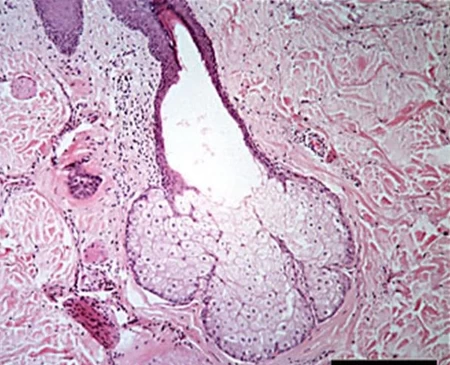

(alvéolos) Epitelio...

(glándulas) Epitelio...

(glandula sublingual) Epitelio...